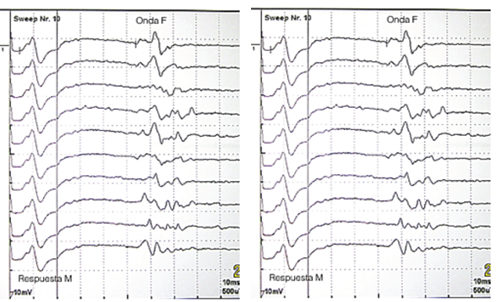

Figura 2. Representación de la latencia de la onda F en el nervio peroneo izquierdo y derecho, en nuestro paciente. Mostrar/ocultar

• Ondas F: onda F del nervio tibial posterior derecho e izquierdo con valores neurofisiológicos normales. Ligero aumento de la latencia de la onda F del nervio peroneal izquierdo –raíz L5, plexo lumbo-sacro– (59,2 ms, normal <56,7 ms). Onda F de nervio peroneal derecho con valores neurofisiológicos normales (Figura 2).

La onda F es un potencial motor pequeño que aparece tardíamente en relación con el potencial de acción o respuesta M, tras la estimulación de un nervio periférico. Su origen obedece a la despolarización directa de las motoneuronas del asta anterior de la médula espinal, a consecuencia del impulso antidrómico que alcanza el cono axónico a partir del sitio de estimulación (Figura 3). Permite evaluar la porción proximal del axón motor. Es útil en la evaluación de los nervios largos y es un indicador de lesión periférica, especialmente de localización proximal, lo cual permite diferenciar una lesión de la raíz nerviosa de una lesión periférica distal3. Es útil en neuropatías proximales o en aquellas en donde de forma temprana no es posible obtener mayor información del segmento proximal, por ejemplo, síndrome de Guillain Barré y en radiculopatías. Si se ajusta el valor de la latencia de la onda F con la longitud de la extremidad, un valor que supere dos desviaciones estándar se puede considerar anormal.

Conclusión del estudio: el informe concluye que tanto la pérdida de amplitud en los músculos de la pierna y pie (tibial anterior, peroneo lateral, extensor hallucis largo y extensor corto de los dedos), como el aumento de la latencia de la onda F en el nervio peroneal izquierdo, son indicativos de una neuropatía del nervio peroneal común izquierdo por bloqueo de este a nivel proximal, a la altura de la cabeza del peroné. El motivo de dicho bloqueo es la compresión mecánica postural debida a la sedestación prolongada con las piernas cruzadas.